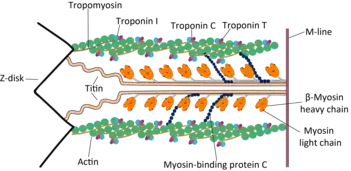

Troponin T (shortened TnT[1] or TropT) is a part of the troponin complex, which are proteins integral to the contraction of skeletal and heart muscles. They are expressed in skeletal and cardiac myocytes. Troponin T binds to tropomyosin and helps position it on actin,[2] and together with the rest of the troponin complex, modulates contraction of striated muscle.[3] The cardiac subtype of troponin T is especially useful in the laboratory diagnosis of heart attack because it is released into the blood-stream when damage to heart muscle occurs.[4] It was discovered by the German physician Hugo A. Katus at the University of Heidelberg, who also developed the troponin T assay.

The troponin complex is responsible for coupling the sarcomere contraction cycle to variations in intracellular calcium concentration. Increased troponin T levels after an episode of chest pain indicates myocardial infarction.[7] It was discovered by the German physician Hugo A. Katus at the University of Heidelberg. He also developed the troponin T assay.[8] In patients with stable coronary artery disease, the troponin T concentration has long been found to be significantly associated with the incidence of cardiovascular death and heart failure, but it was 2014 before it began to be accepted as a predictor of who would later suffer acute myocardial infarction (heart attack).[9][10]